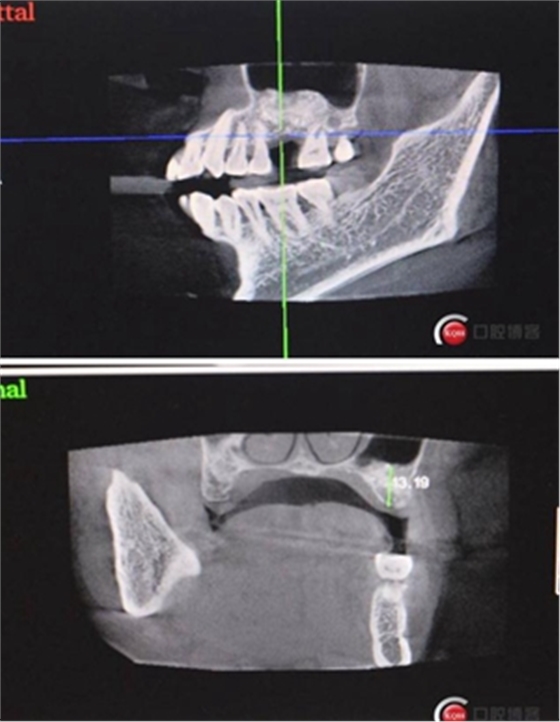

大家好,我是梁老師的助理小依。由于梁老師每天手術(shù)檔期安排較滿,加上經(jīng)常出差講課,沒有時間整理病例 。為了方便大家更及時的了解梁老師最新手術(shù)動態(tài),以后將由我為大家整理并推送梁老師最新經(jīng)典案例。案例文字旁白少,但圖片會盡量完整展示手術(shù)全過程,供大家學(xué)習(xí)參考。有任何問題,可以留言,梁老師會親自為大家解答。感謝大家對梁老師的支持和關(guān)注!